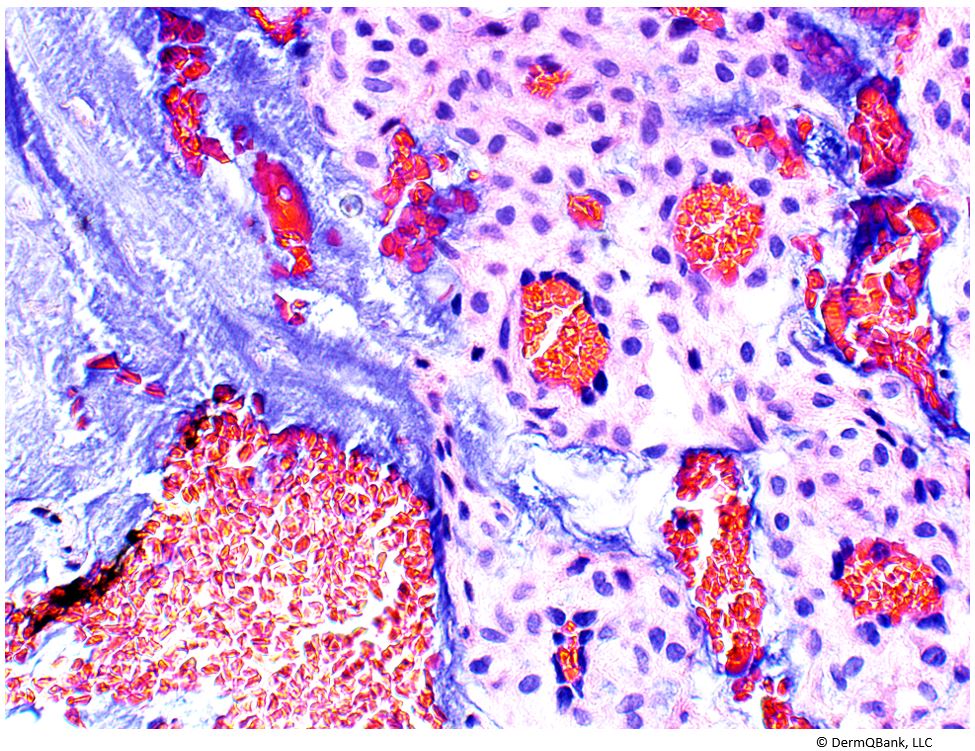

Cryoglobulinemia is caused by circulating immunoglobulins, immunoglobulin complexes, or immunoglobulin/protein complexes which reversibly precipitate in the cold. Type I cyroglobulinemia leads to vasculopathy, which clinically presents as purpura, Raynaud's syndrome, acrocyanosis, retinal hemorrhages, and/or other signs of thrombosis. It is caused by circulating single monoclonal immunoglobulins (usually IgG or IgM), which reversibly precipitate in the cold. Type I cryoglobulinemia is usually associated with underlying myeloma or B-cell malignancy. Conversely, Type II and III cryoglobulinemia are mixed cryoglobulinemias that lead to leukocytoclastic vasculitis clinically presenting as inflammatory palpable purpura.

Type I cryoglobulinemia causes vasculopathy with signs and symptoms associated with thrombosis rather than vasculitis (e.g., Raynaud’s syndrome, acrocyanosis, non-palpable purpura).